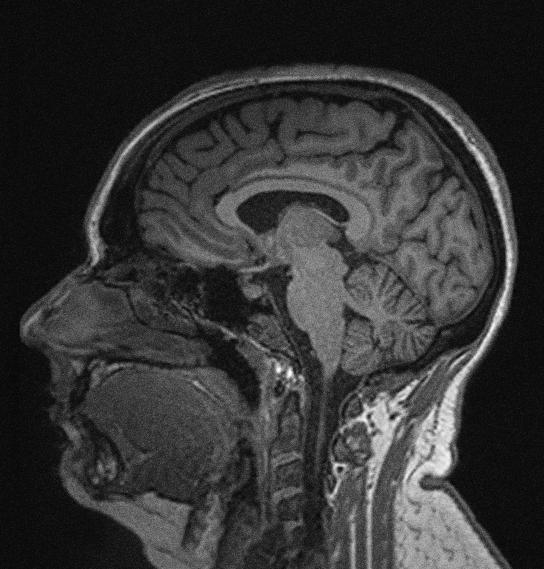

L’imagerie par résonance magnétique (IRM) est une technique d’imagerie le plus souvent utilisée à des fins cliniques, mais qui constitue aussi un outil fondamental de recherche en neurosciences. Les séquences IRM permettent d’explorer différents aspects de la structure et du fonctionnement du cerveau.

La capacité des technologues en IRM à réaliser les examens dans des conditions sécuritaires et agréables pour les participants de la recherche, ainsi qu’à créer des images cérébrales de haute résolution influencent directement la qualité du travail des chercheurs. C’est grâce à une excellente collaboration entre technologues en IRM et chercheurs que nous développons, au Centre de recherche CERVO, de nouveaux protocoles de neurostimulation individualisés par l’IRM.

Dans le cadre de notre protocole de recherche, nous localiserons précisément, grâce à l’IRM, l’aire cérébrale visuelle (V2, ou aire associative de Brodmann 18 et 19) qui sera stimulée par SMTr. En fournissant des données cérébrales structurelles acquises en IRM (séquence T1-MPRAGE) au robot SMTr, nous lui permettrons de venir cibler très précisément la zone visuelle censée s’éteindre lors de l’écoute attentive d’informations auditives.

Par ailleurs, les images d’IRM de type T1 (figure 6, à gauche) permettront aux chercheurs d’inférer exactement d’où viennent les modifications de l’activité cérébrale entraînées par la SMTr chez les participants au protocole de recherche. Grâce à certaines techniques d’analyse (méthode de reconstruction de sources), il est possible de déterminer de quelle zone du cerveau provient le signal électrique enregistré grâce à l’EEG. Lorsque les images anatomiques sont disponibles pour chaque participant, la précision des analyses augmente considérablement. En utilisant ce type d’analyse et en comparant des groupes d’individus jeunes et âgés, nous pourrons déterminer si notre protocole permet de rajeunir le fonctionnement cérébral, et, si oui, dans quelles zones précises du cerveau

ce phénomène est-il observable. Ce protocole de recherche prévoit également l’acquisition d’images de diffusion (figure 6, à droite). Ces images permettent d’étudier la structure des fibres de matière blanche, les tracts qui, dans le cerveau, relient les différentes zones de matière grise entre elles. Grâce à ce type d’images, les chercheurs pourront déterminer si les caractéristiques structurelles des faisceaux de matière blanche jouent un rôle dans la réponse à la neurostimulation chez les individus jeunes et chez les aînés. On peut par exemple imaginer que l’intégrité structurelle des faisceaux de matière blanche reliant les zones du cerveau impliquées dans l’attention (p. ex. : les faisceaux longitudinaux supérieurs I, II et III) sera positivement corrélée à l’effet bénéfique induit par le protocole de neurostimulation, et ce, indépendamment de l’âge des participants.